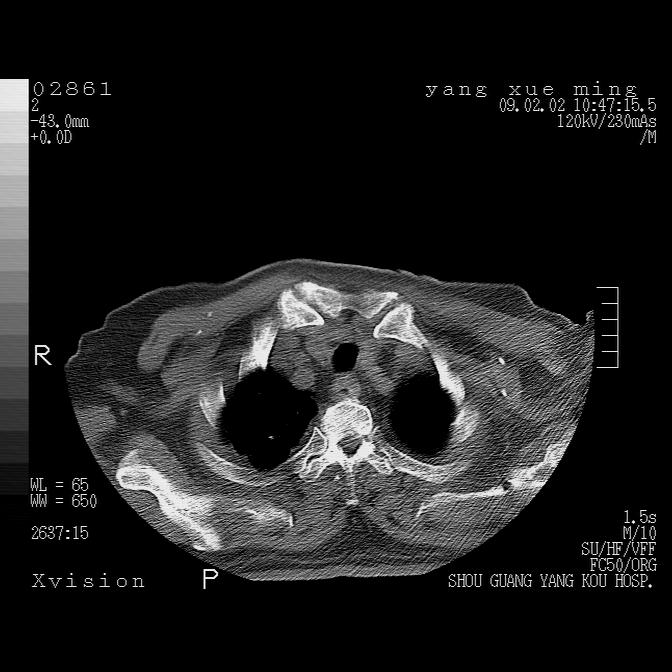

以下是引用lkc8963在2009-2-3 20:11:00的发言:[br]1)右上肺陈旧病灶。2)右下肺团块及团片影,影像表现符合感染。3)左心增大,左冠脉钙化,符合冠心病。4)双侧肺门扩大,以左侧为著,肺动脉干略粗,左上肺局限性气肿,为谨慎起见,需除肿瘤,建议增强。

以下是引用lkc8963在2009-2-3 20:11:00的发言:[br]1)右上肺陈旧病灶.2)右下肺团块及团片影,影像表现符合感染.3)左心增大,左冠脉钙化,符合冠心病.4)双侧肺门扩大以左侧为著,肺动脉干略粗,左上肺局限性气肿,为谨慎起见,需除肿瘤,建议增强.